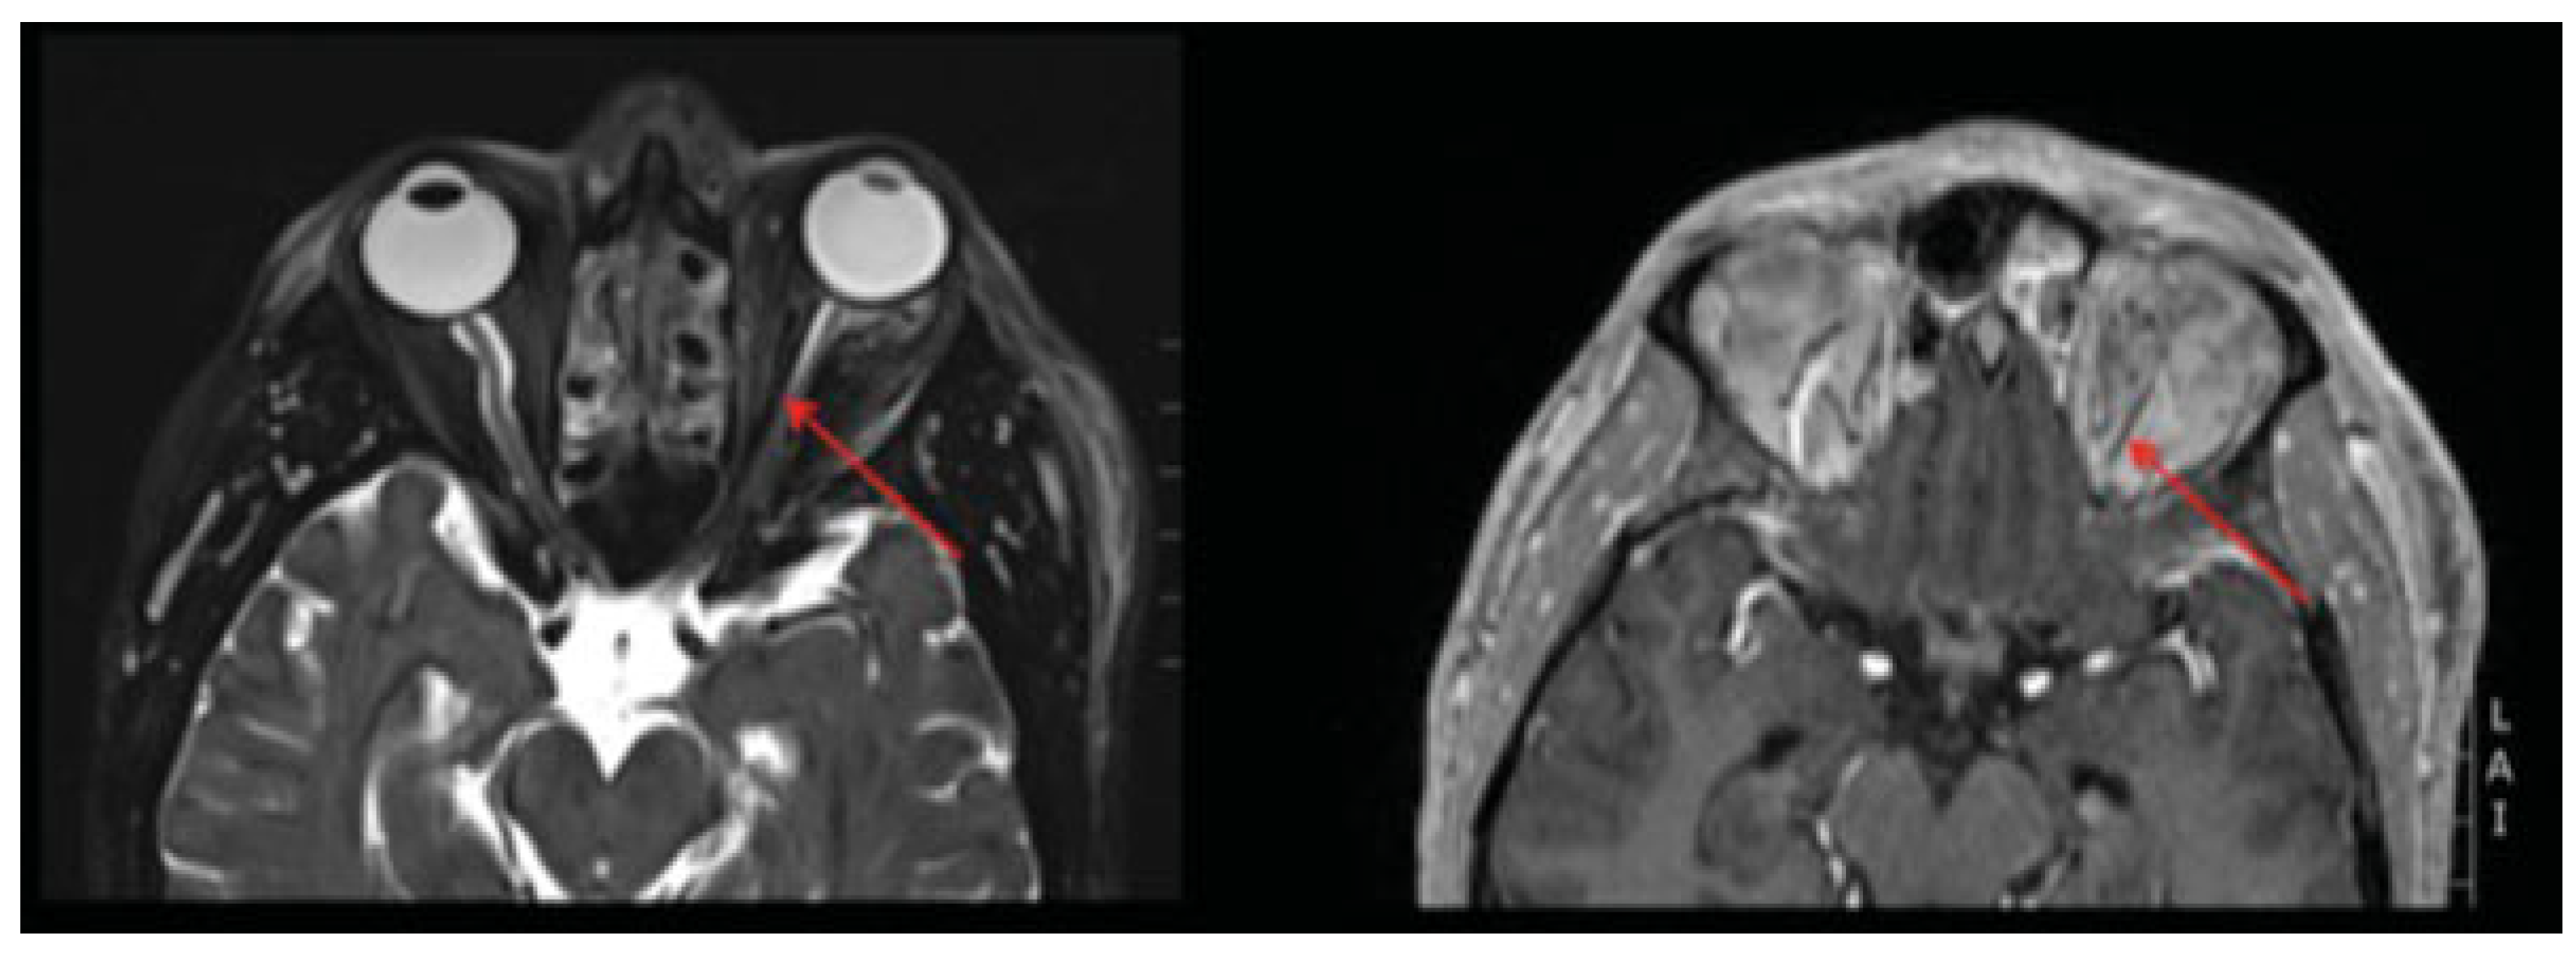

The patient was taken emergently (within 40 min of symptom onset) to the operating room for orbital decompression and hardware removal (no imaging was obtained at this time due to the clear clinical diagnosis and necessity of urgent operative management). This was accomplished via the same transconjunctival incision with an additional lateral canthotomy. Intraoperatively, there was no evidence of intraorbital hematoma, active hemorrhage, or old clot. The orbital floor plate was removed, and a portion of the orbital floor and medial wall excised to aid with decompression. Postoperative imaging was notable for removal of the hardware and bony decompression, without evidence of retrobulbar hemorrhage, but mild proptosis of the left globe (Figure 4). The optic nerve was noted to mildly stretched, secondary to intraorbital edema.

Immediately following decompression, the patient was noted to have a persistent afferent pupillary defect OS. Intraocular pressures were 11 mm Hg OD and 38 mm Hg OS. High-dose steroids were initiated to assist with edema control. The intraocular pressure in the left eye continued to improve following decompression and was 15 mm Hg 8 h after decompression. He continued to be examined serially by the surgical and ophthalmology teams. There was no improvement in light perception in the left eye. A subsequent magnetic resonance angiogram, taken on postoperative day 1, demonstrated infarction of the left optic nerve (Figure 5). The patient subsequently underwent bony decompression of the optic canal. He was followed and had no recovery of visual acuity at 6 months postdecompression (20/400 OS).

Figure 4. Postdecompression computed tomography. There has been interval removal of the orbital floor implant and some of the bony floor, with significant edema and proptosis of the left globe.

Figure 5. Postdecompression magnetic resonance angiography. T2-weighted image (left) and fat saturated image (right) infarction of the optic nerve (arrows).